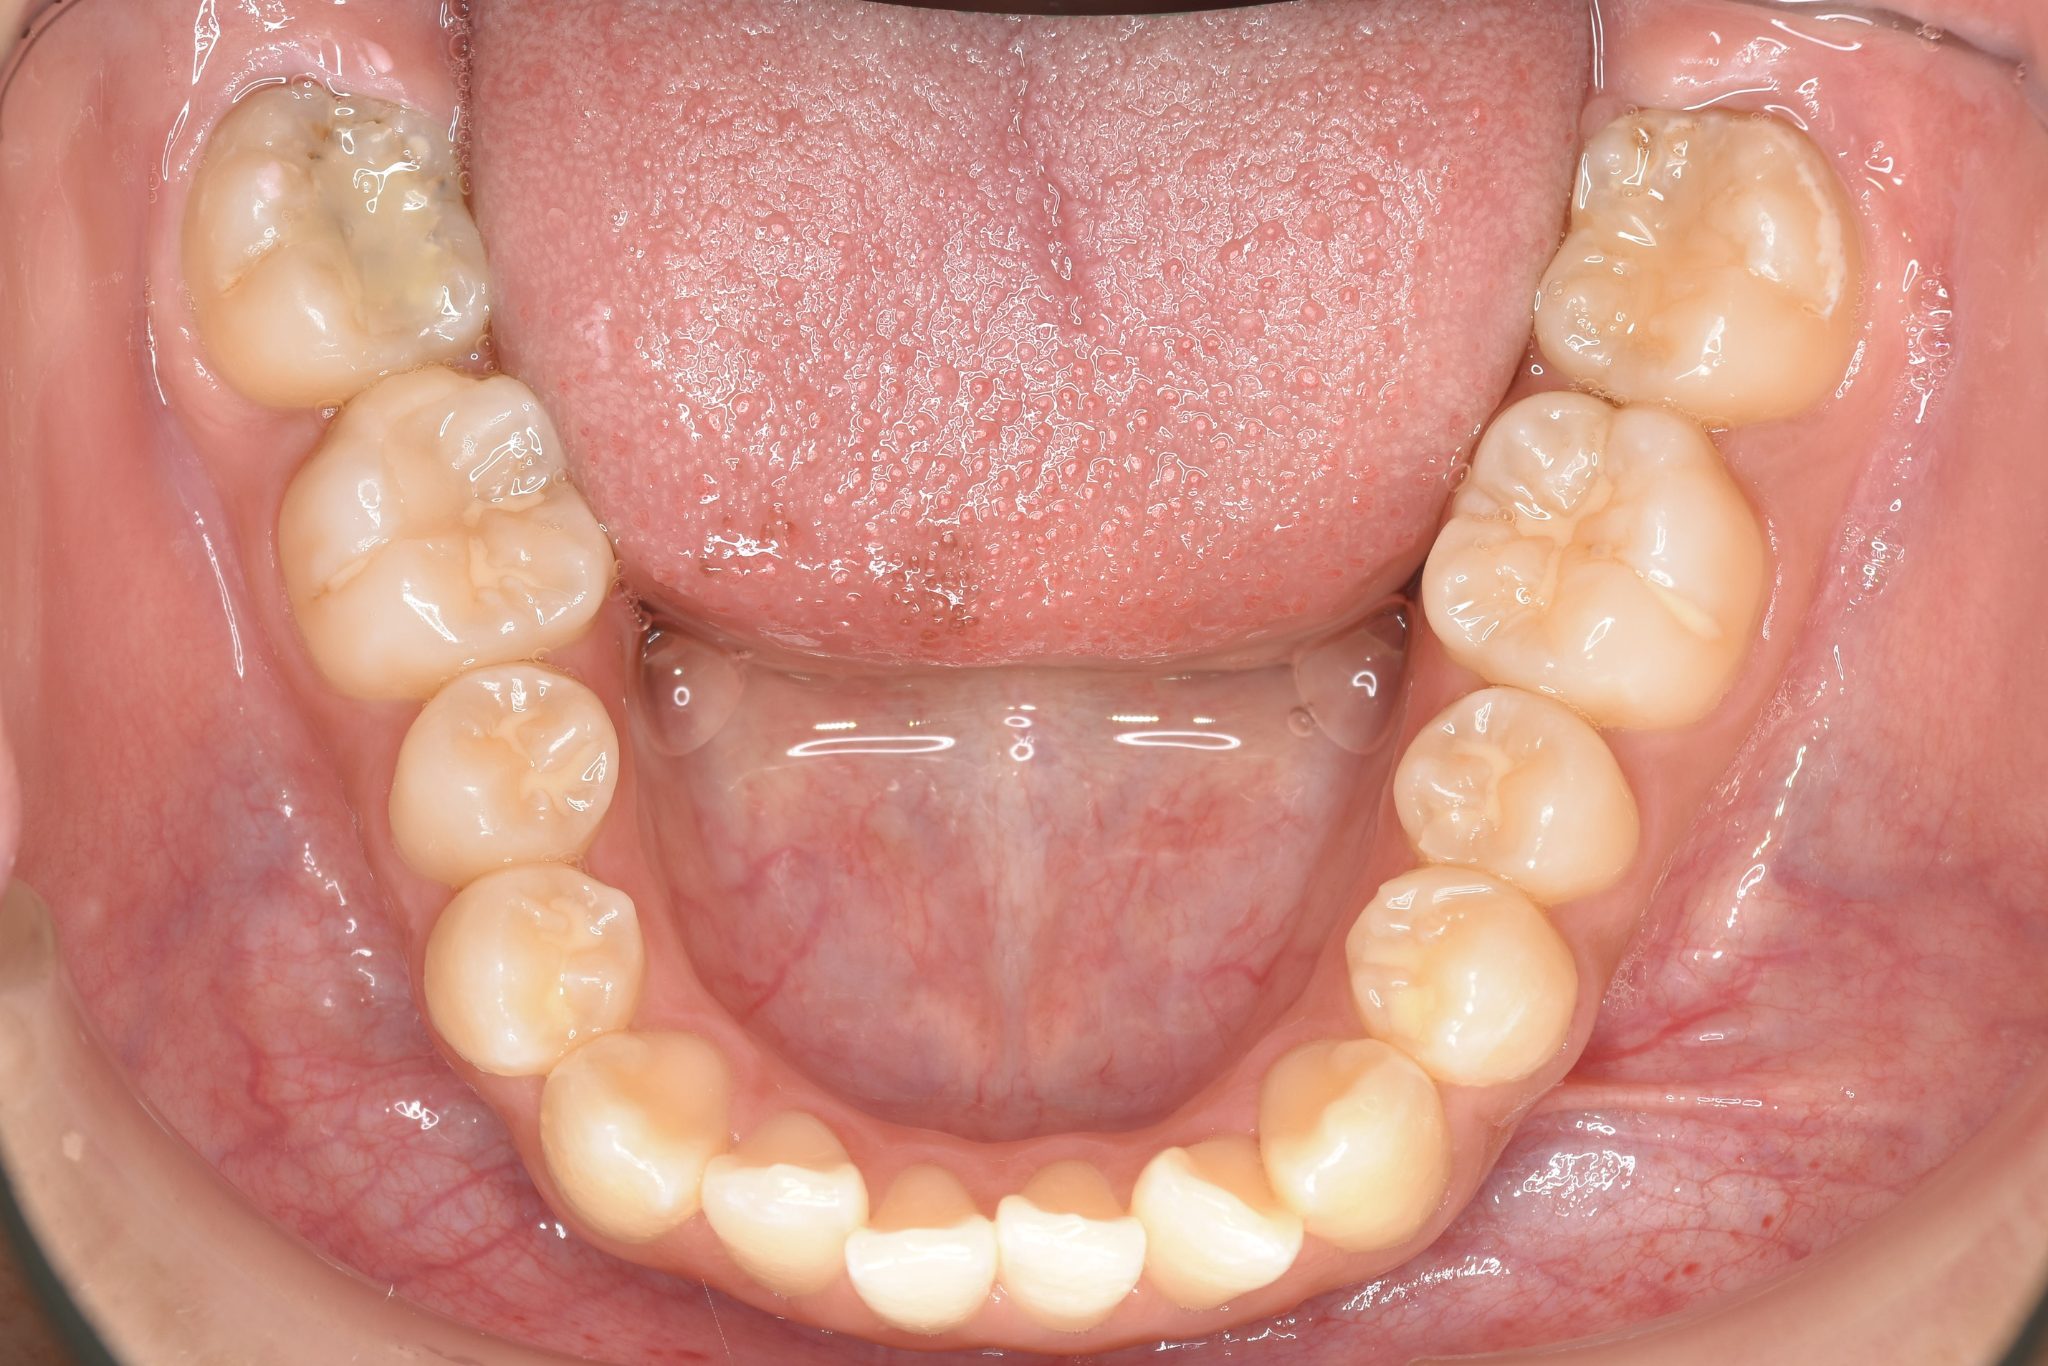

ビフォー

アフター

主訴 前歯の歯並び

施術内容 成人矯正1期治療

治癒期間 1年2か月間

費用 954,800円(税込)